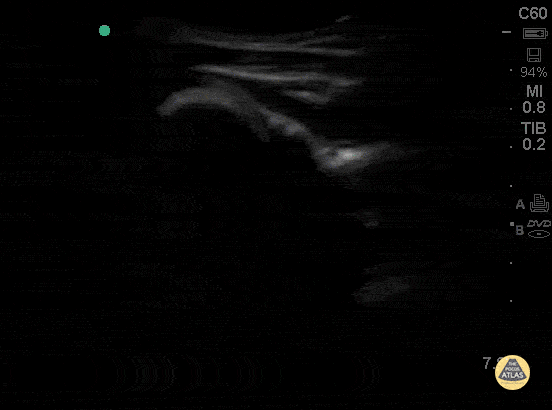

Shoulder dislocations can also be visualized on ultrasound. Start posterior and visualize the humerus then move it upward and medially until you can see the humeral head.

In this picture you can see the rotator cuff (red), humeral head (green) and glenoid (purple).

And here is the shoulder rotating

And what a dislocated shoulder looks like, space between the glenoid and the humeral head.